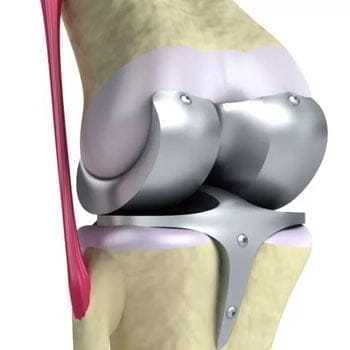

Упрощенная схема установки импланта.

Единственная тактика лечения, которая дает результаты - эндопротезирование. Индустрия выпускает модернизированные имплантаты под требования любого пациента. Искусственные конструкции создаются из биосовместимых материалов, представленных керамикой, инновационными сплавами металлов и высокомолекулярным полиэтиленом, которые не оказывают токсического, аллергического и канцерогенного воздействия на окружающие структуры.

Самый распространенный тип импланта коленного сустава.